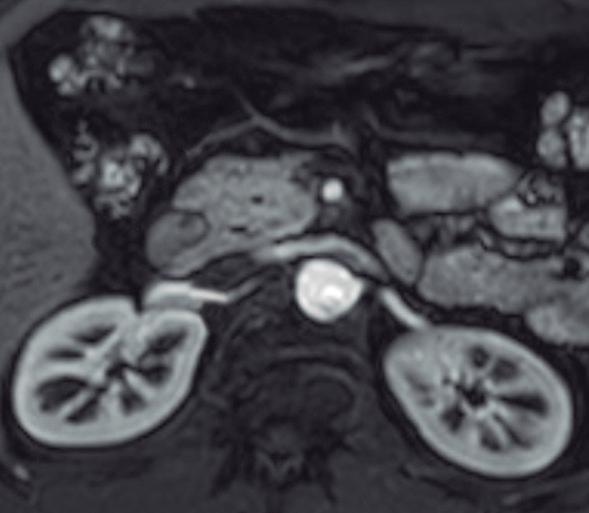

En las imágenes encontramos parénquima pancreático rodeando a la 2° porción duodenal, habitualmente en toda su circunferencia y en ocasiones de manera incompleta. En la colangio-RM es posible visualizar al conducto pancreático a la derecha del duodeno, con un recorrido que se dirige a la ubicación de la papila mayor (Figura 9).17

A) Resonancia magnética secuencia T1 con gadolinio, plano axial. Las flechas señalan el parénquima del páncreas prolongado hacia la derecha “abrazando” a la 2° porción duodenal (cabeza de flecha). B) Resonancia magnética, secuencia T1 con gadolinio, plano axial, corte más caudal al previo. Las flechas nos muestran al páncreas rodeando de manera completa a la 2° porción del duodeno. C) Resonancia magnética, secuencia T2, plano coronal. La flecha señala presencia de parénquima glandular y conducto pancreático a la derecha del duodeno (cabezas de flecha). D) Resonancia magnética, secuencia T2, plano coronal, corte posterior al previo. El páncreas anular y su conducto de drenaje rodean en forma completa al duodeno (cabezas de flecha). E) Colangio-RM. El conducto del páncreas ventral (flechas) hace un giro, rodea al duodeno (cabeza de flecha) y se une al conducto pancreático principal para drenar en la papila mayor. F) Colangio-RM. La imagen magnificada muestra con mayor detalle el recorrido del conducto de Wirsung en el contexto de un páncreas anular.